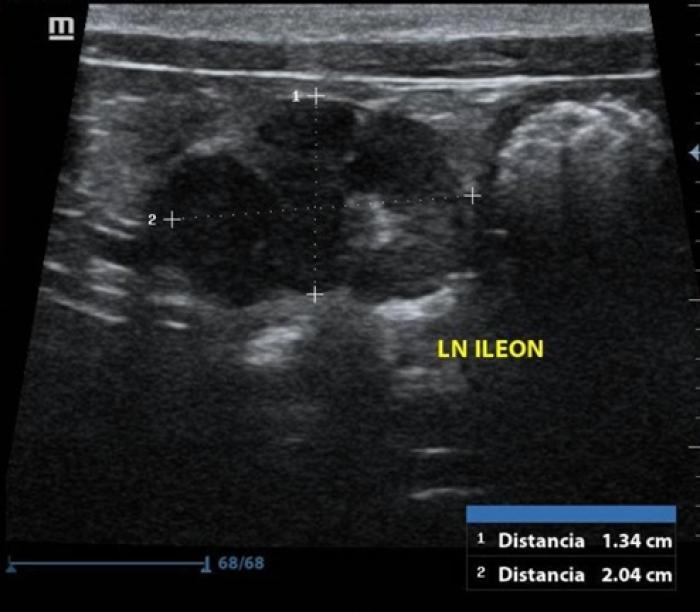

en urianálisis presentó una DU de 1.038, presencia de sangre secundario a la toma de muestras y proteinuria relacionada. Presión arterial promedio de 152/92, considerado como pre hipertensión, perfil tiroideo sin alteraciones y en ultrasonido abdominal se observa engrosamiento del segmento intestinal del duodeno (0.30 cm), yeyuno en mediciones normales y engrosamiento del íleon (0.39 cm) con pérdida de la estratificación normal, presencia de linfonodos iliacos reactivos y presencia de sedimento en el lumen de la vesícula biliar (Figuras 2 y 3). El coproparasitoscópico directo fue negativo y la tinción kinyoun fue positiva aCryptosporidium.

Química sanguínea: urea disminuida (5.6 mmol/l),los demás analitos dentro de rangos normales, hemograma sin alteraciones. Ultrasonido abdominal con ayuno de 8 h en el cual se observó estómago con presencia de gas, engrosamiento de segmentos duodenal (0.39 cm) (Figura10)y yeyunal (0.30-0.31 cm), el yeyuno con pérdida de definición de capas, así como la presencia de linfonodos yeyunales reactivos, con grasa perinodal hiperecoica y peritoneo reactivo adyacente al yeyuno (Figura11),vesícula biliar con presencia de sedimento biliar en cantidad moderada.

Los signos clínicos, así como los hallazgos que suelen observarse en el ultrasonido abdominal tales como aumento en el grosor de las capas intestinales, pérdida de definición de las capas, linfadenopatía reactiva y peritoneo hiperecoico son comunes para ambas enfermedades, por lo que en ningún caso se debe emitir un diagnóstico por este método ni basado en signología clínica. El promedio de las mediciones de la pared intestinal de ambos gatos superaron los 0.28 cm, por lo cual se justificaron la toma de las biopsias. La prueba gold standard para la diferenciación de las enteropatías crónicas felinas es el examen histopatológico de muestras de biopsias teñidas con H&E5.